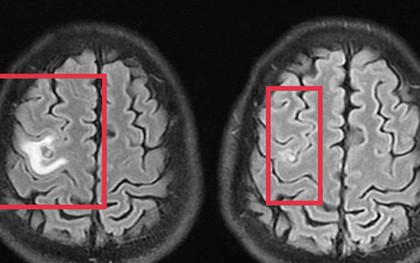

Đi khám sau 2 tuần liên tục đau đầu âm ỉ, mệt mỏi, nữ bệnh nhân ở Hà Nội phát hiện mắc áp xe não trái nên cần nhập viện điều trị.